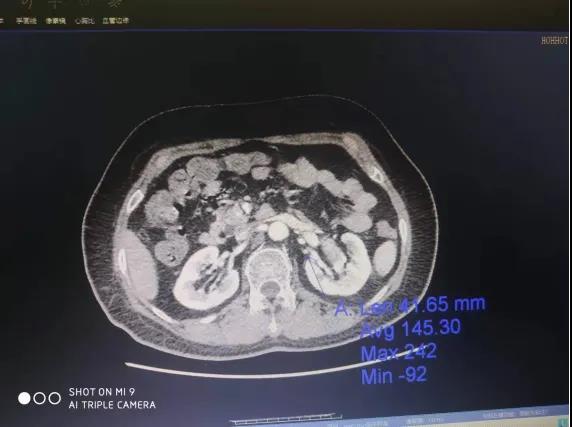

患者,女性,61岁,因体检发现左肾肿物一周收入院,入院后行全腹部增强CT检查回报:左肾下极肿瘤。大小48*47mmhg,肿瘤分期:T1bM0N0,肿瘤位于肾实质深部,上极紧贴肾门,各期影像显示患肾血供复杂:包括肾动脉、副肾动脉各一支。

肾静脉两支

变异血管分布如下:

第四腰椎椎前血管发出的侧支动脉一支

穿过后腹膜入肾上极变异动脉一支(来源于脾动脉)

肿瘤回流静脉一支(内有癌栓)